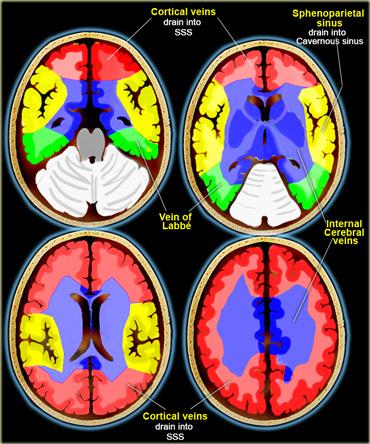

Tuy nhiên, nhồi máu tĩnh mạch có phân bố điển hình riêng, như được minh họa ở hình bên trái.

Do nhiều tĩnh mạch là các cấu trúc đường giữa, nhồi máu tĩnh mạch thường có tính chất hai bên.

Điều này gặp trong huyết khối xoang tĩnh mạch dọc trên, xoang thẳng và các tĩnh mạch não trong.

Bên trái là hình minh họa các vùng dẫn lưu tĩnh mạch.

Các vùng này có sự biến đổi đáng kể và hình minh họa chỉ nên được xem như một hướng dẫn tham khảo mang tính tương đối.